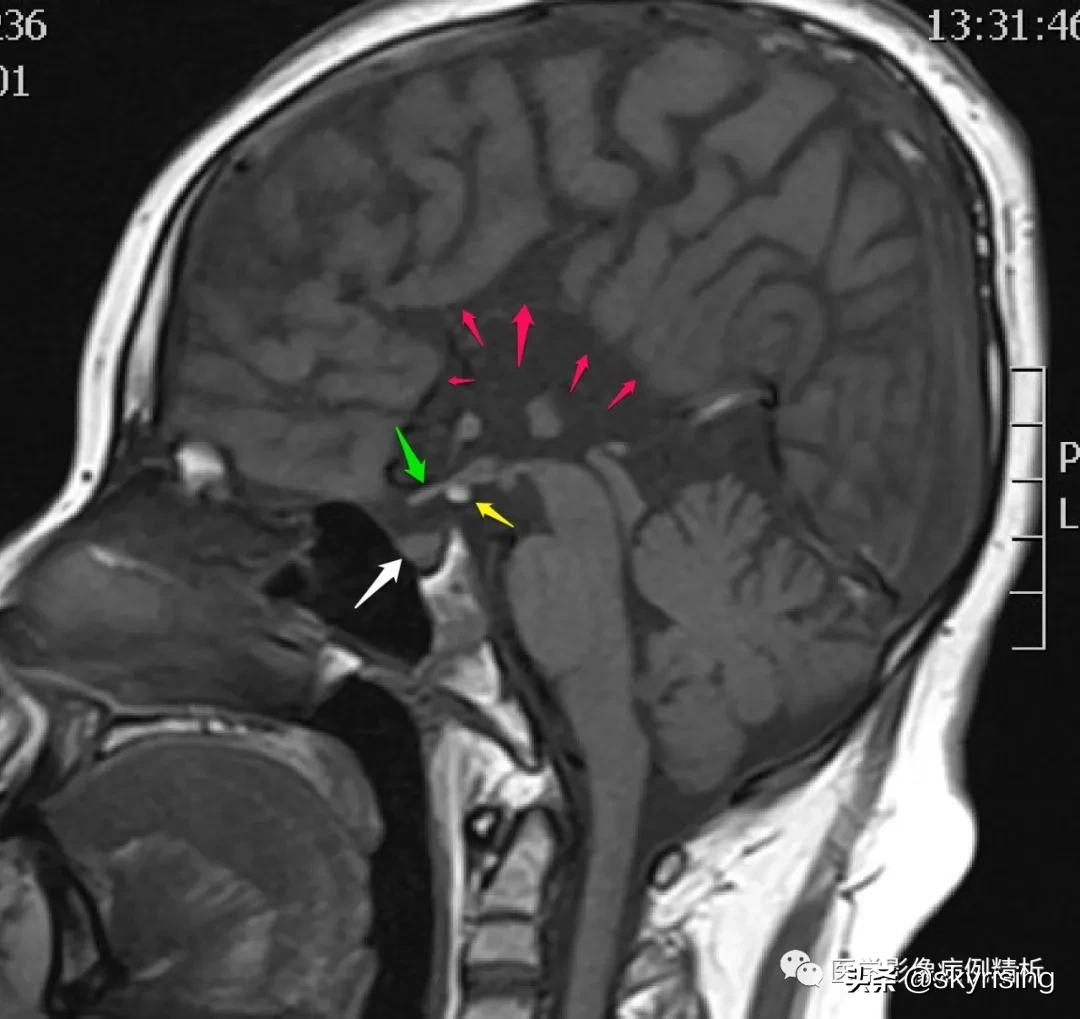

T1WI矢状位如下图所示,本例患者确诊为垂体柄阻断综合征并胼胝体缺如、垂体后叶异位。两图为相邻的矢状位正中图像,可以清晰显示缺如的胼胝体,如红色箭头所示区域,未能看到正常的扣带回内翻形成扣带沟,第三脑室上抬、侧脑室正常形态消失。绿色箭头为视交叉,黄色箭头结节状高信号为异位的垂体后叶,白色箭头所示为垂体前叶,正常鞍区后方的垂体后叶上移至黄色箭头区域。